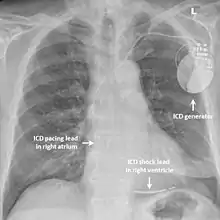

Desfibrilador automático implantable

En aquellos con síndrome de QT corto que ya han experimentado un ritmo cardíaco anormal potencialmente mortal, como la fibrilación ventricular, se puede recomendar un desfibrilador cardioversor implantable (DCI) para reducir la posibilidad de muerte súbita[3] Este dispositivo se implanta debajo de la piel y puede monitorear continuamente el ritmo cardíaco. Si el dispositivo detecta una alteración peligrosa del ritmo cardíaco, puede administrar una pequeña descarga eléctrica con el objetivo de restablecer el ritmo. Implantar un DCI en alguien con síndrome de QT corto que aún no ha experimentado una arritmia potencialmente mortal es más controversial, pero se puede considerar.[6][1]